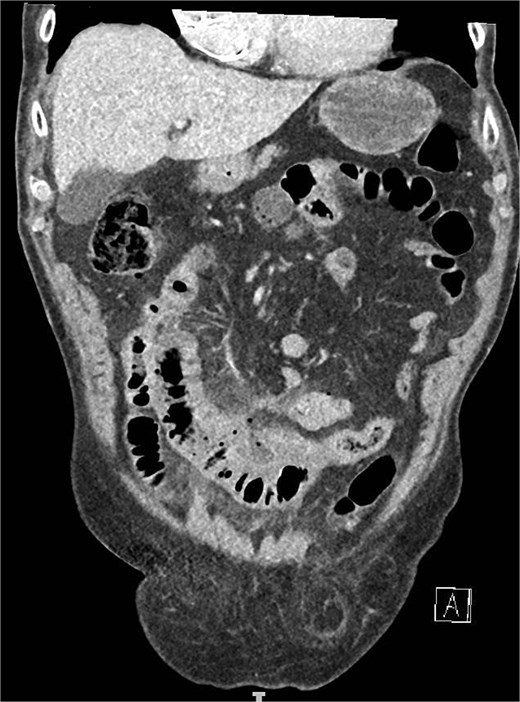

A computed tomography angiography (CTA) of the abdomen was performed, it showed a long segment of the small bowel with wall thickening in the right lower quadrant, accompanied by a inflammatory change in the mesenteric fat with multiple air bubbles, and free fluid in the pelvis, suggestive of hollow organ perforation (Fig. 1). Given the high suspicion of hollow organ perforation and clinical signs of peritonitis, an indication for exploratory laparotomy was established and performed as an emergency procedure. An antibiotic therapy with piperacillin/tazobactam was empirically initiated preoperatively.

CTA showing a long segment of small bowel with inflammatory wall thickening and fat stranding of the mesentery with multiple air bubbles.